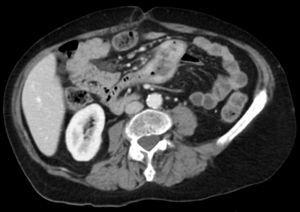

Paciente de sexo femenino, de 66 años, consulta por dolor abdominal de 2 meses de evolución (figs. 1 y 2).

Figura 1